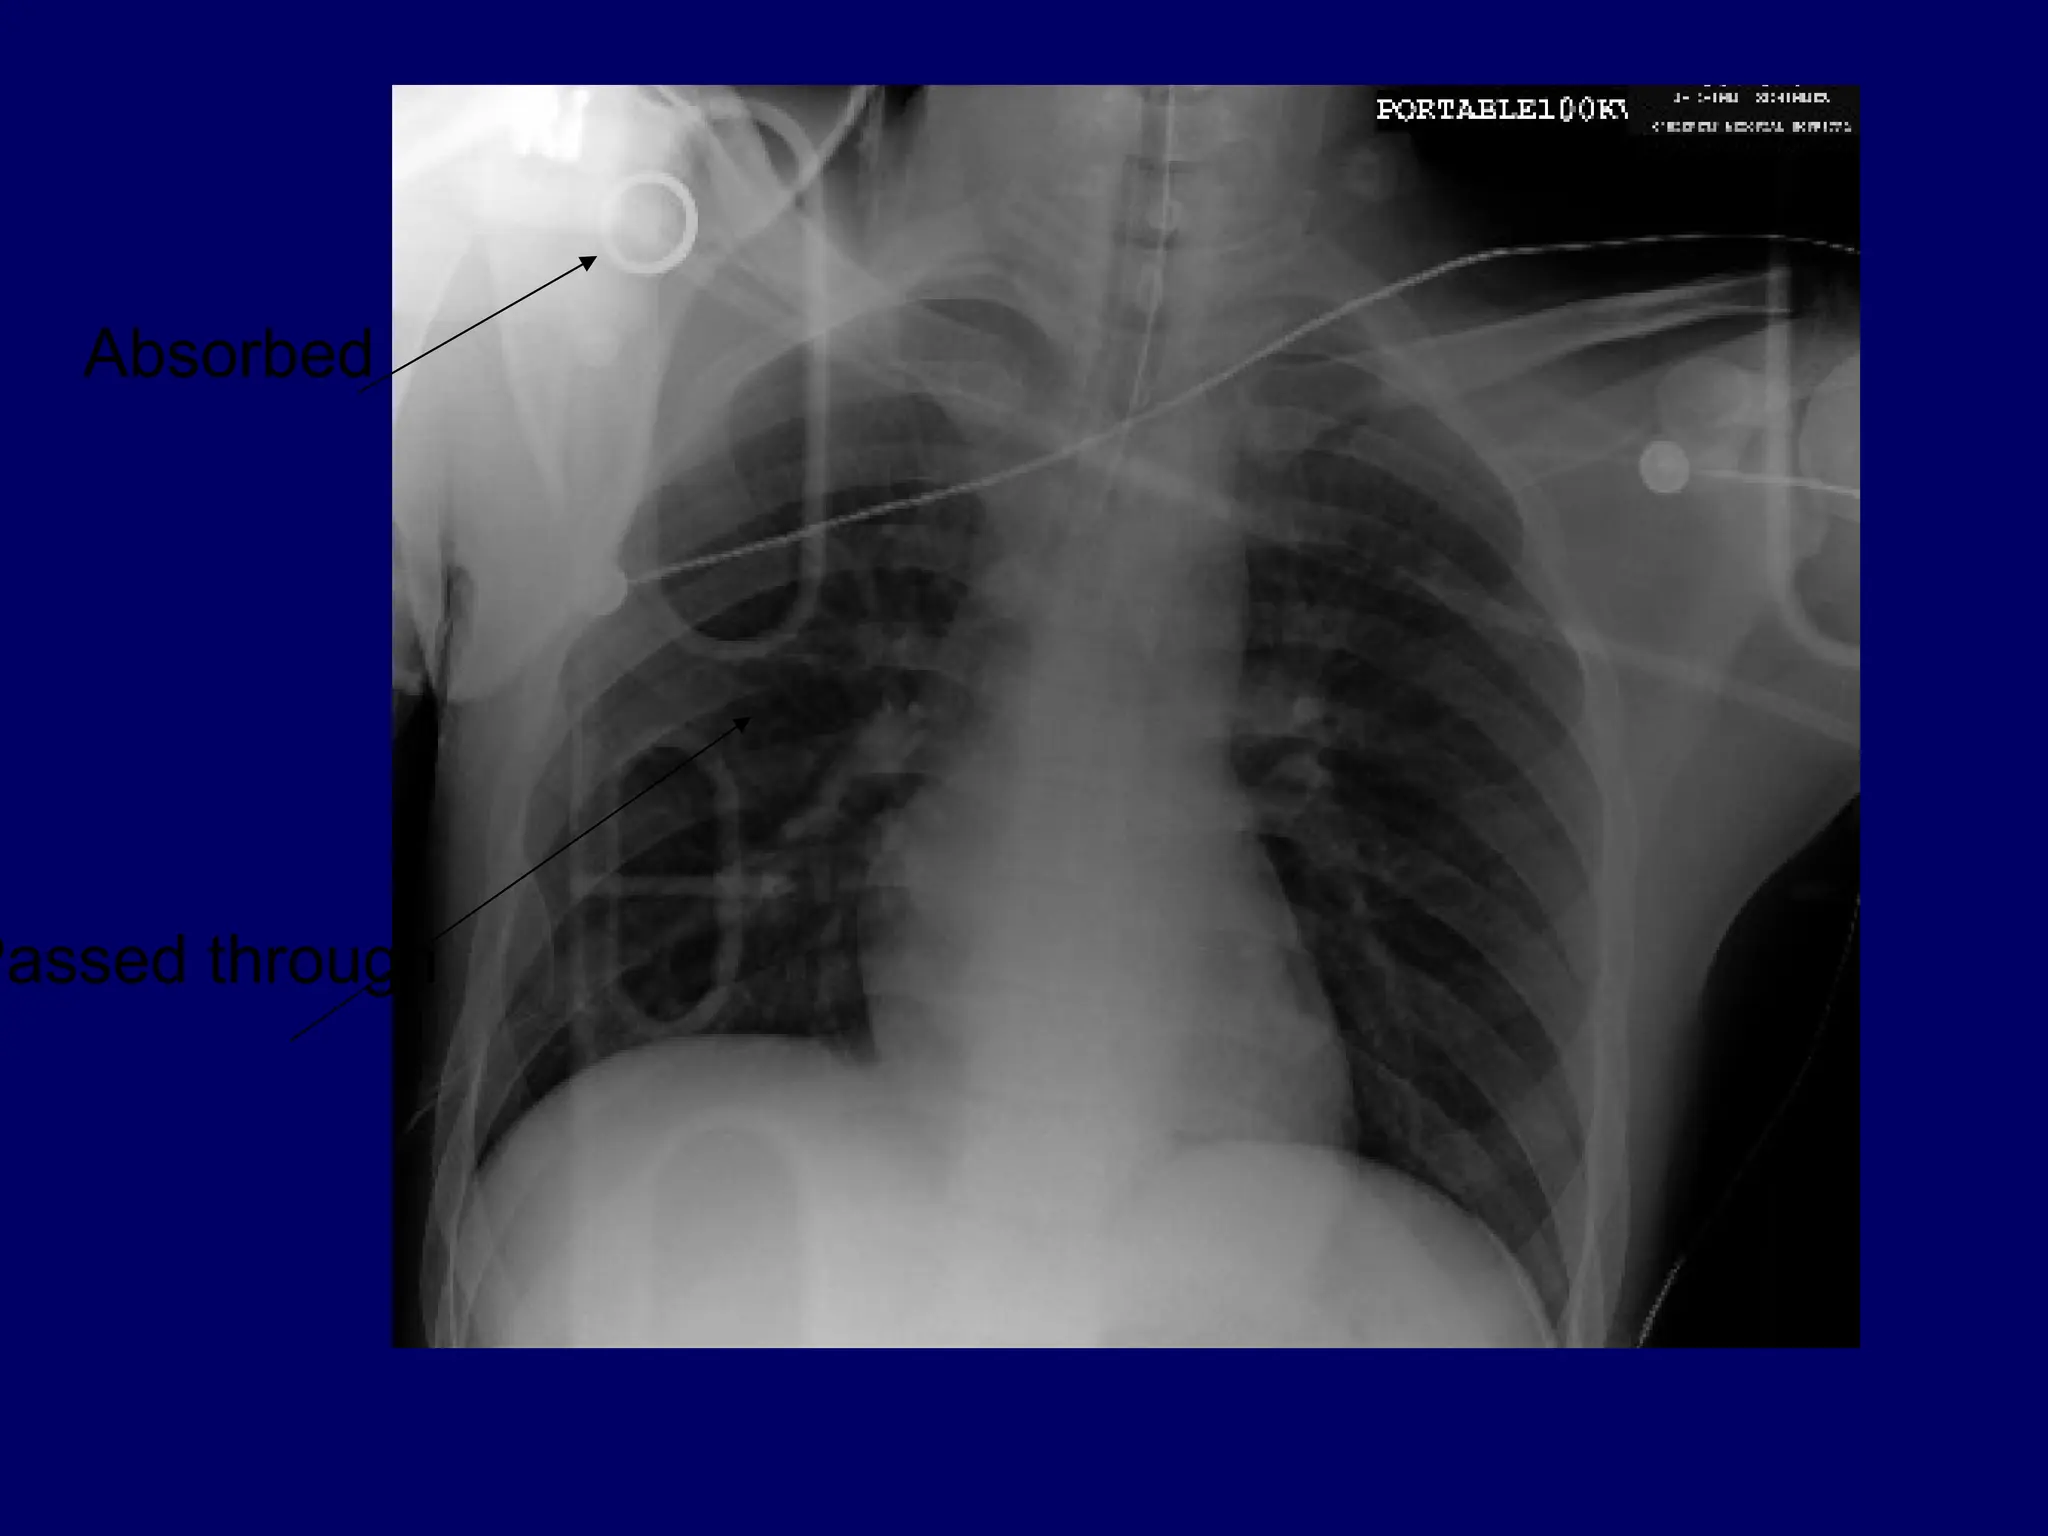

Absorbed

Passed through

Medullary bone

Soft tissue

Metal

A broken centralvenous catheter has migrated into the right lower lobe pulmonary artery